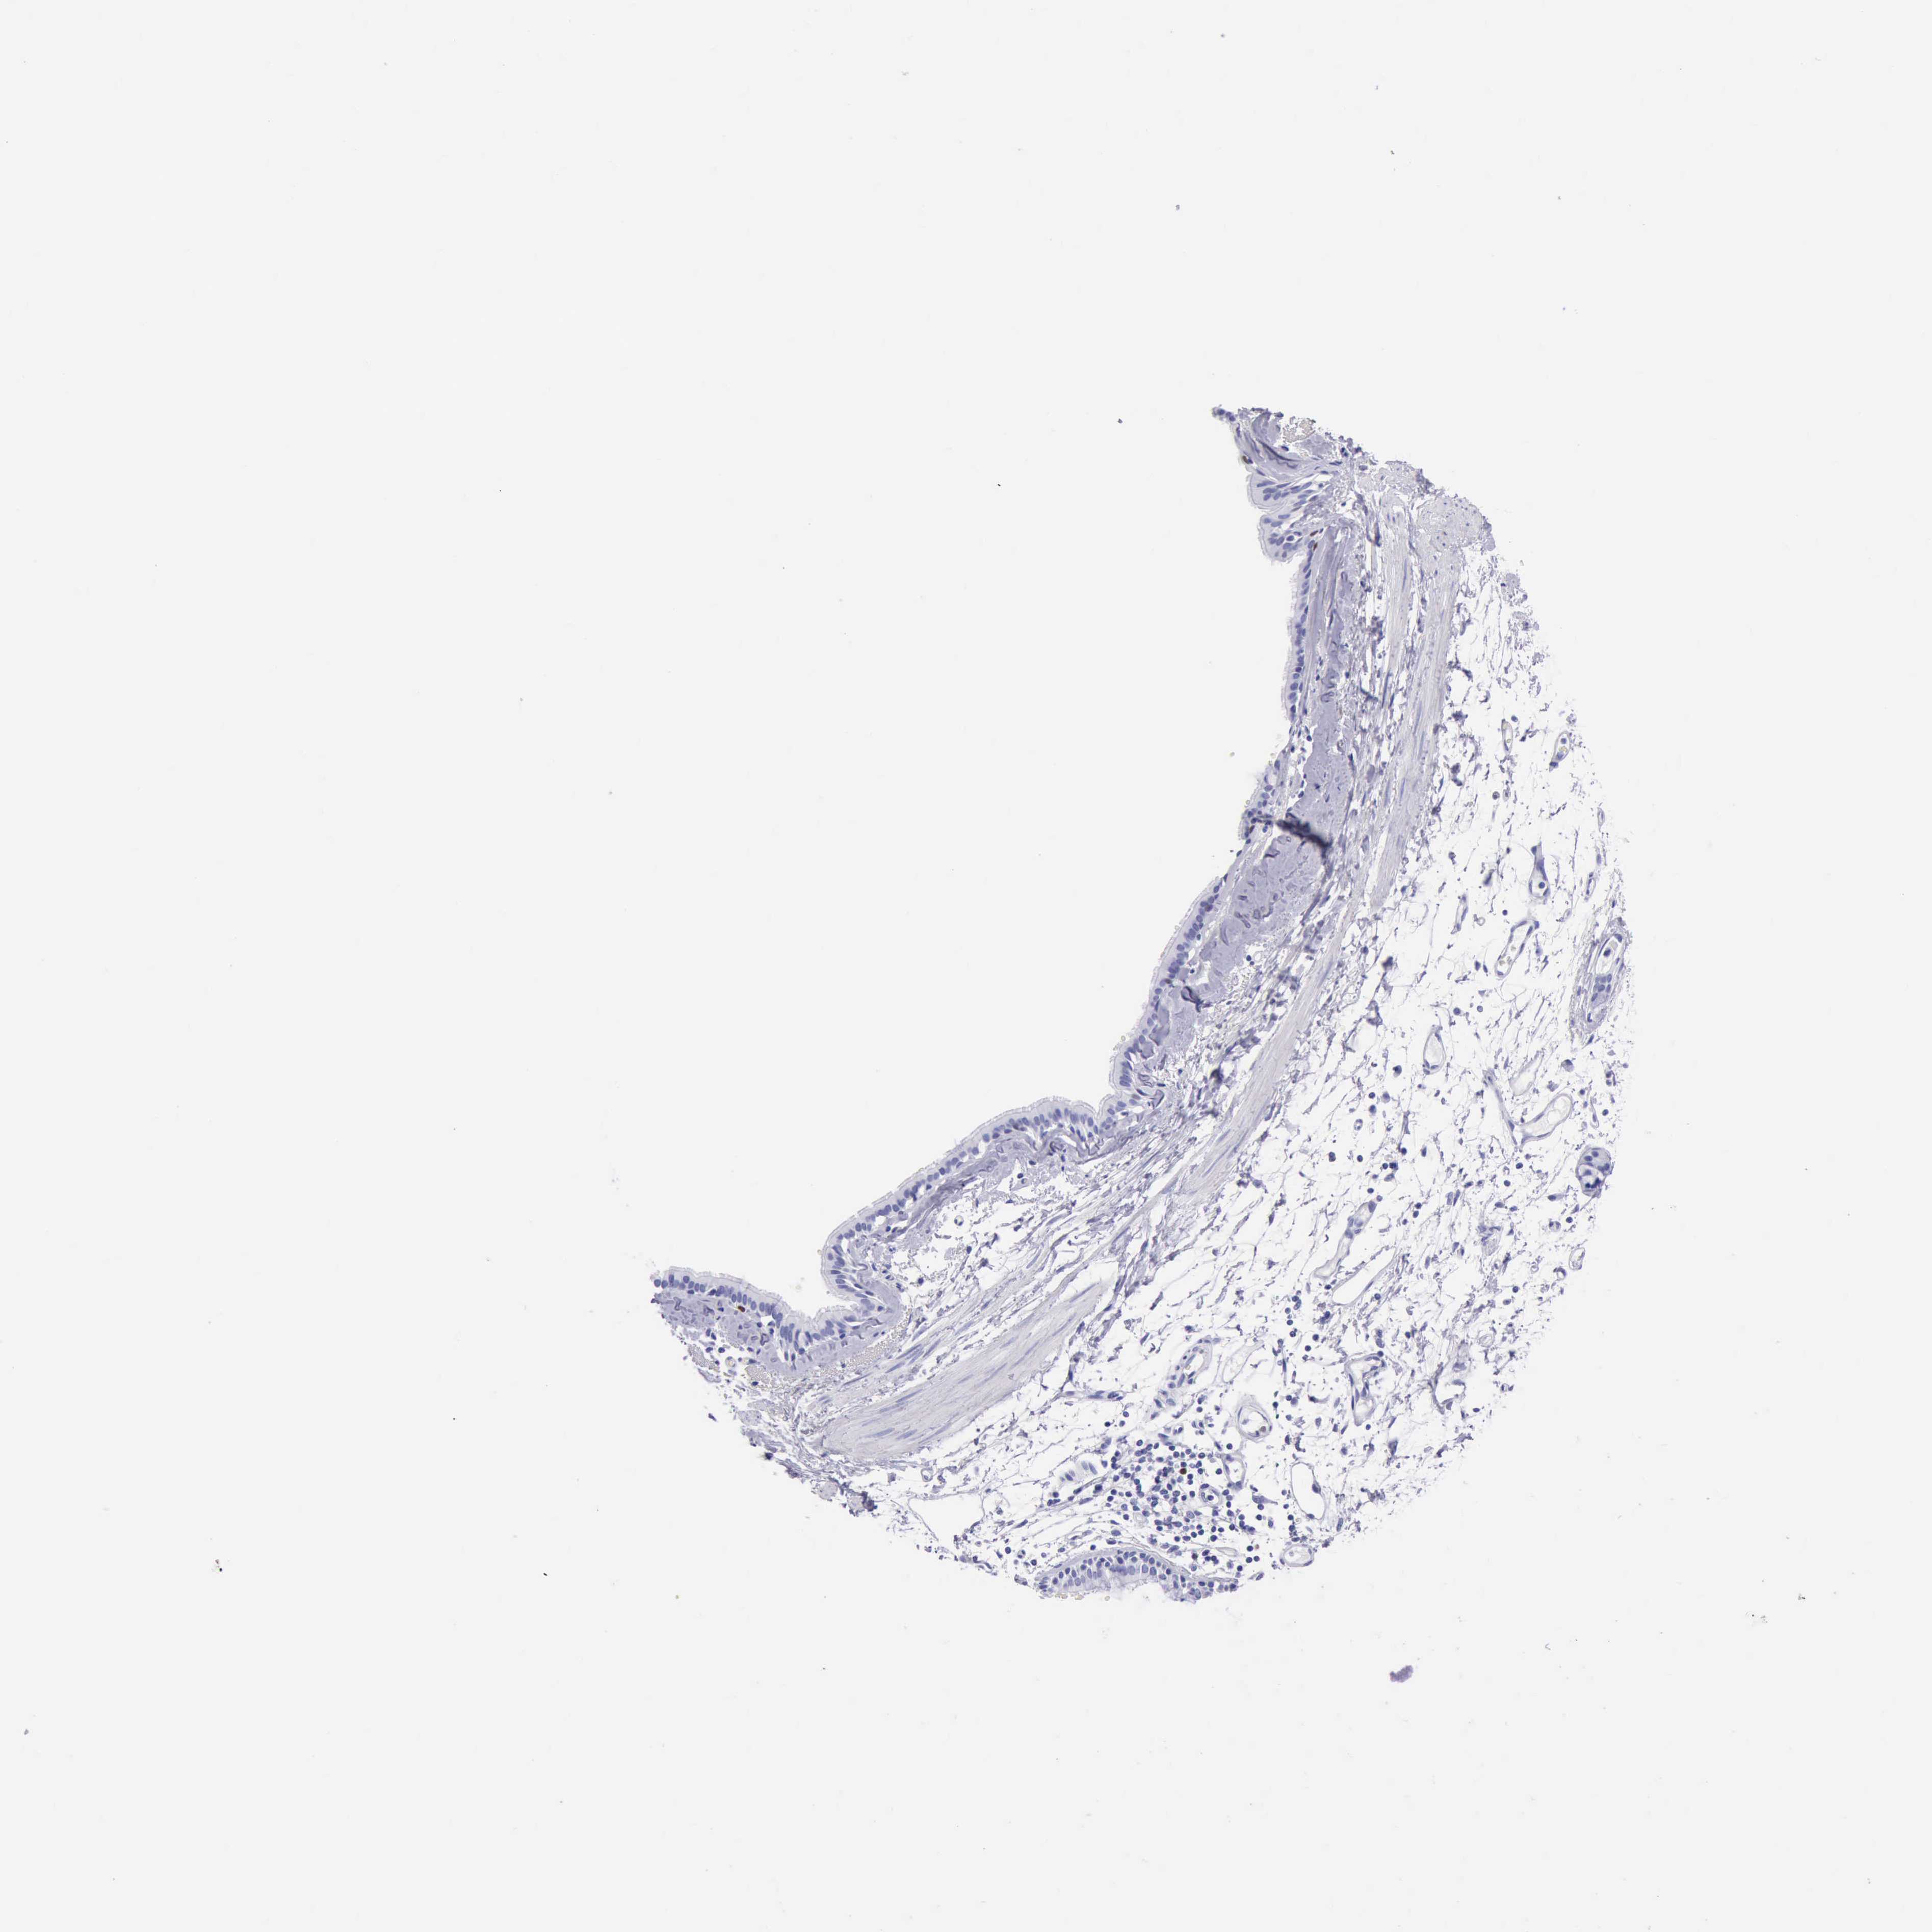

BRONCHUS